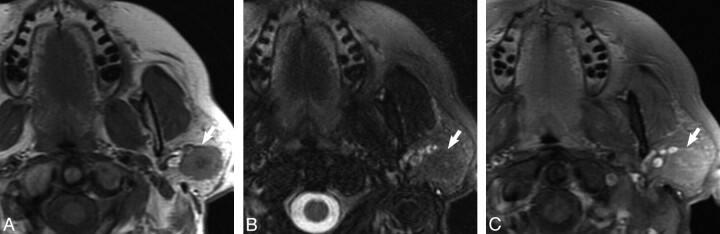

Fig 1.

Case 1, 62-year-old female with 2-year history of firm, painless left parotid mass. A, Axial T1-weighted MR image shows a well-demarcated mass within the superficial lobe of the left parotid gland (white arrow) that is T1 hypointense. B, Axial T2-weighted MR image with fat saturation shows the mass (white arrow) to be isointense to the native parotid gland. C, Axial T1-weighted postgadolinium sequences illustrates the mass (white arrow) as isointense to the native parotid gland.